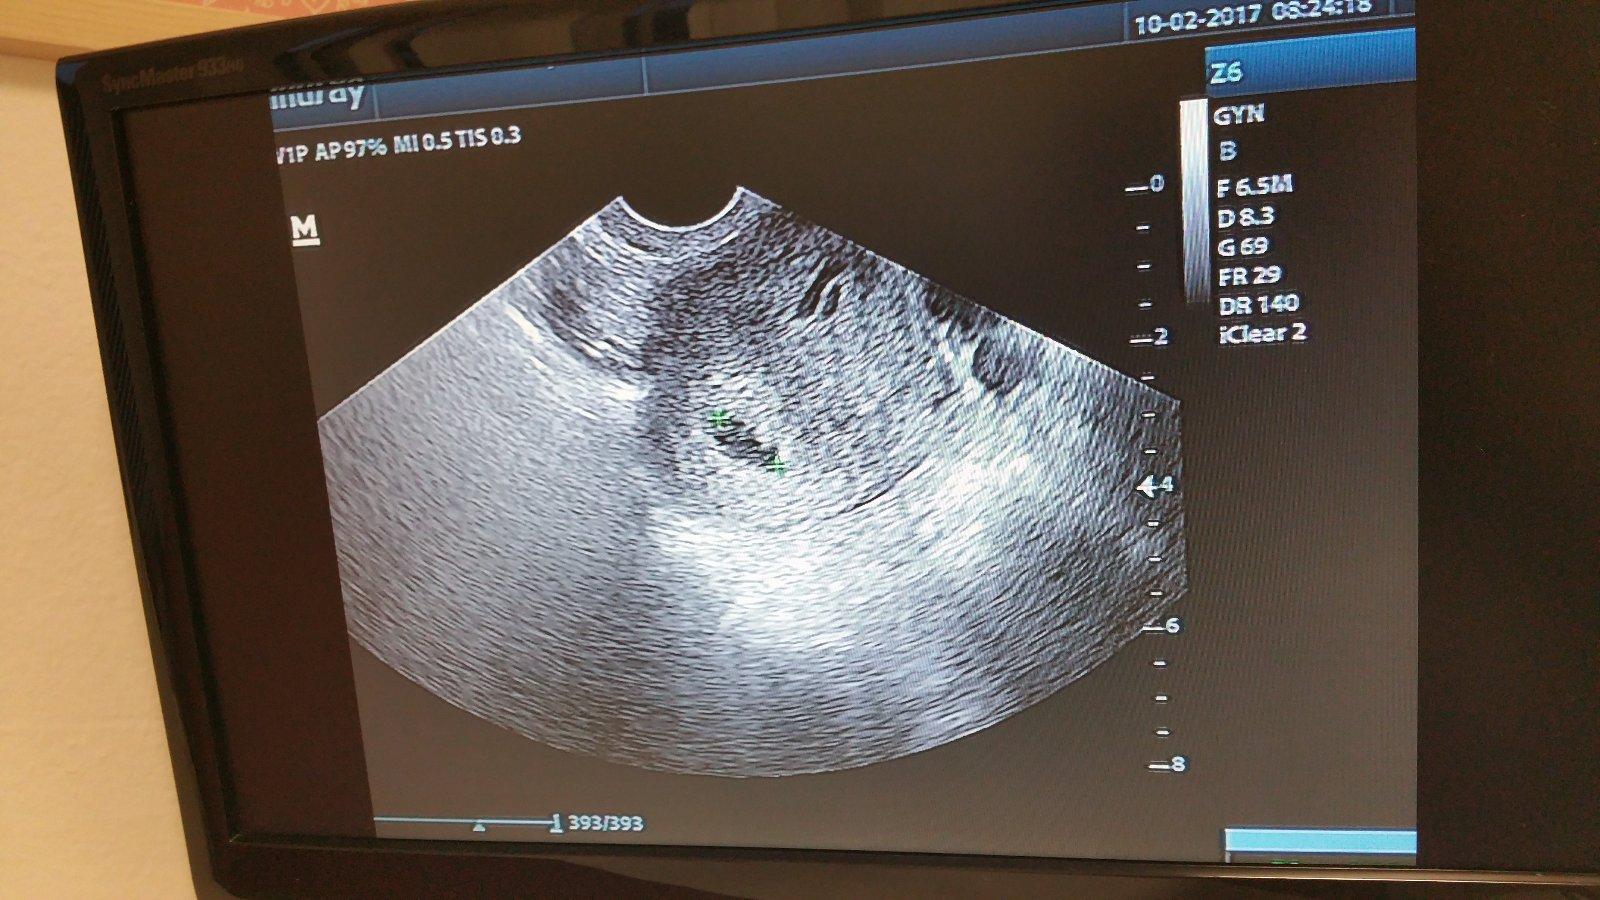

@maja129 som v 5tt. Duphaston som si dala teraz rano 1 tab. este neviem ako sa budem po nom citit 🙂 dufam ze nam pomoze a babenko donosime az do stastneho konca. A ako si sa citila pred tym nez si zacala brat duphaston?